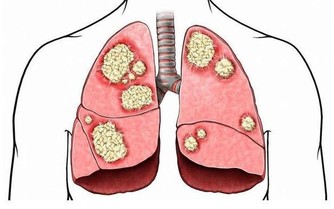

當年紀漸大,血管內膜會慢慢增厚,形成「斑塊」,動脈狹窄,導致心管阻塞。

過去,這樣的心血管疾病好發於老年人,然而隨著生活、飲食型態改變,疾病好發年齡層逐年下降,當斑塊結在血管分支的路口,血流過不去,容易發生閉塞,後果將不堪設想。

當發生急性血栓阻塞時,人會感覺到腿突然疼痛。此時,一般可以確定是血栓突然脫落造成的,這樣的情況是非常危險的,因為如果血栓隨血流遊離到心臟處,發生堵塞,就會導致心肌梗塞。所以,建議每個人都做一下這個測試,來檢測你是否有血管阻塞的情形吧!